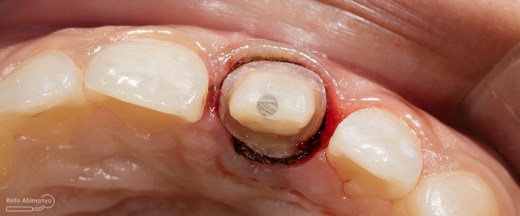

Kondisi setelah crown dibongkar

Foto klinis setelah selesai preparasi dan siap cetak

Foto klinis setelah preparasi dari arah insisal